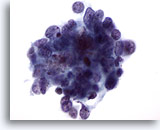

画像 1

肺FNA、単純ヘルペスウイルス肺感染症

多核化、核の相互圧排、スリガラス様クロマチンのほか、好酸性の核内封入体などウイルス性細胞変性に特徴的な様相が認められます。

60倍

画像 1

肺FNA、単純ヘルペスウイルス肺感染症

多核化、核の相互圧排、スリガラス様クロマチンのほか、好酸性の核内封入体などウイルス性細胞変性に特徴的な様相が認められます。

60倍